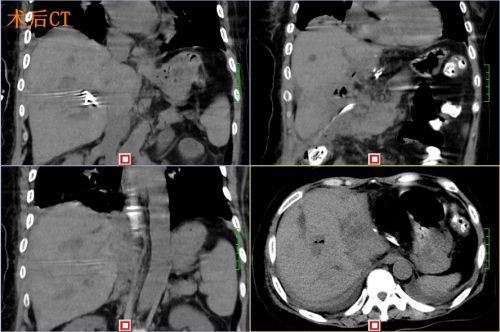

术后ct

术后,为了让患者迅速恢复健康,彭湘群护士长为尹女士制定了快速康复护理计划并认真落实。患者术后第一天就下床活动,并很快恢复正常饮食,没有并发症发生。

国际肝胆胰协会中国分会胆道结石专业委员会主任委员、湖南省普外腹腔镜医疗质量控制中心主任尹新民教授表示:我国是肝胆管结石高发地区,每年有很多患者饱受这一疾病的痛苦,这台手术是目前国内完成最复杂的全肝结石腹腔镜手术。(微创外科通讯员:徐晓平 彭湘群)